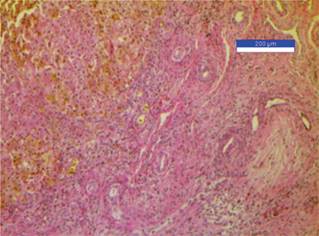

La biopsia hepática permite confirmar el diagnóstico en 97-98% de los casos. En ella, los hallazgos más típicos son proliferación de los conductos biliares, fibrosis portal y estasis biliar canalicular. En los casos precoces es posible observar escasos conductos biliares en lugar de proliferación, por lo que ante la sospecha clínica se recomienda realizar biopsias seriadas.3

En la exploración física con TA 80/40 mmHg, FC 115 lpm, FR 36 rpm, T 37 oC, SatO2 92%, Peso 5 kg, Talla 59 cm. Se observa tinte ictérico en conjuntivas, mucosas y piel (Kramer 3), hepatomegalia de 4 × 4 × 4 cm, resto de la exploración sin alteraciones. Se solicitan laboratorios a su ingreso reportando BT 7.2 mg/dL, BD 4.28 mg/dL, BI 2.92 mg/dL, TGP 128 mg/dL, TGO 216 mg/dL, FA 1198 mg/dL, GGT 680 mg/dL y DHL 259 mg/dL. Se ingresa a quirófano para realización de laparotomía exploradora con toma de biopsia, con diagnóstico de ictericia progresiva y síndrome colestásico tardío. Durante la cirugía se observa hígado con cirrosis moderada y remanente de vía biliar, por lo que se realiza derivación portoentérica. Estudio histopatológico de hígado y remanente de árbol biliar extrahepático reportando colestasis y fibrosis extensa (estadio III/IV) secundaria a atresia de vía biliar extrahepática con conductos menores a 100 micras de diámetro (Figura 1).

El gammagrama hepatobiliar (sensibilidad 82% y especificidad 91%) y colangiografía no han demostrado ser mejores que el ultrasonido de vía biliar, puesto que tienen varias limitantes, entre ellas su disponibilidad.3 De acuerdo con los hallazgos ultrasonográficos, debe realizarse una cirugía de forma temprana para restablecer el flujo biliar y prevenir el desarrollo de cirrosis y disfunción hepática.12 Con la finalidad de mejorar el pronóstico del paciente a largo plazo, se obtienen resultados óptimos si se realiza la corrección quirúrgica antes de los 2 meses de vida, siendo el momento ideal antes de 45 días de vida.3 El diagnóstico definitivo se realiza mediante la toma de biopsia seriada.8 La histología es de suma importancia para el pronóstico, ya que se ha reportado el beneficio de ductos > 300 micras para una evolución favorable.10